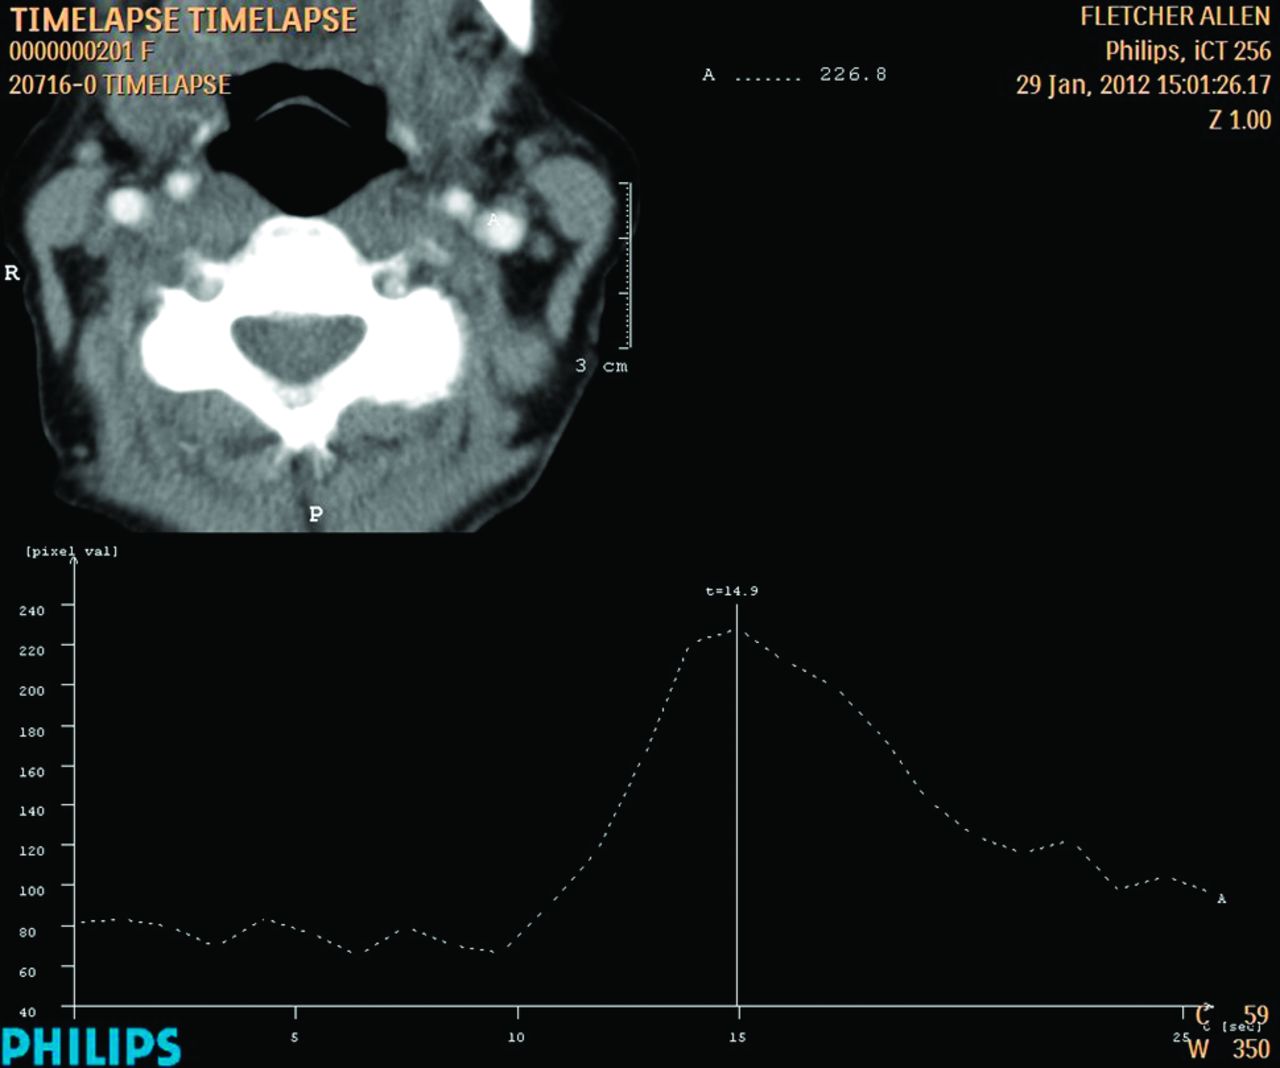

When perfusion CT is performed, the CTP data are used to generate a time-attenuation curve by placing the region of interest over the ICA. The time-to-peak enhancement of the arterial time attenuation curve is determined by choosing the peak enhancement level and assessing the time after injection at this point (typically approximately 16 seconds). For the combination CT angiograms of the head and neck typically performed with CTP, 2 seconds is subtracted from this time (typically approximately 14 seconds).

When CTP is not performed, a time-attenuation curve is generated over a single cervical carotid level (typically C3-C4). After the injection of 15 mL of iodinated contrast material (Isovue 370) and a 15-mL saline chaser, a series of dynamic 1-per-second low-dose scans (80 kV, 100 mAs) is obtained. Contrast material is injected at 6 mL/s. A region of interest is then placed over the ICA to generate the time-attenuation curve (Fig 1). The time-to-peak enhancement of the arterial time-attenuation curve is determined by choosing the peak enhancement level and assessing the time after injection at this point (typically approximately 14 seconds). For combination CT angiograms of the head and neck, this time is used as the scanning delay. For CT angiograms of the head alone (circle of Willis), 2 seconds is added to the time (yielding a total scanning delay of 16 seconds after initiation of contrast injection, for example). Once the appropriate scanning delay has been determined, CTA is performed with 50 mL of iodinated contrast material (Isovue 370 I/mL) followed by a 50-mL saline bolus chaser at 6 mL/s injection rate. Scanning parameters for CTA are as follows: number of detectors, 256; gantry rotation time, 0.5 seconds; caudocranial acquisition; collimation, 0.625 mm; 0.985 pitch; 120 kV; 300 mA. The 64-detector protocol uses the same gantry rotation time, collimation, pitch, kV, and mA, and the only difference is the number of detectors (ie, 64). Acquired data are then reconstructed at 0.9-mm thickness with a 0.45-mm reconstruction interval for evaluation of the vasculature, whereas the 0.625-mm raw data images are used to create MIP images.

Time-attenuation curve obtained during preparation for 256-detector CT angiography of the cerebrovasculature. The time attenuation curve reveals peak contrast at approximately 15 seconds (typically 14 seconds). For CTA of the neck (or CTA of the head and neck), this is the timing used as the scanning delay from the start of contrast injection. For CTA of the head only, 2 seconds is added (17 seconds in this example) to the delay time.